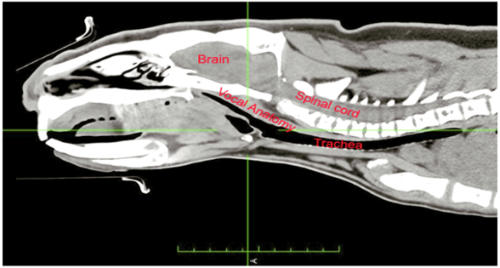

In the more conventionl 2d CAT scan image below, you can see a section through vocal cord anatomy of a male wombat know as KIAL